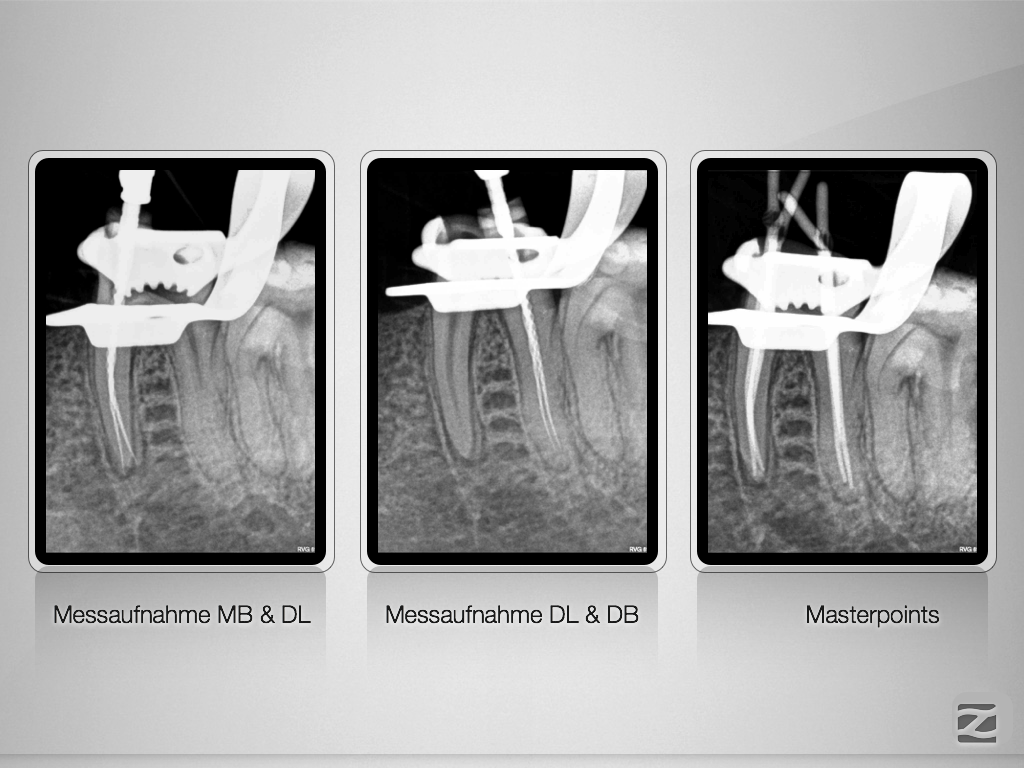

36D.008

Anatomie unterer Molaren (10)